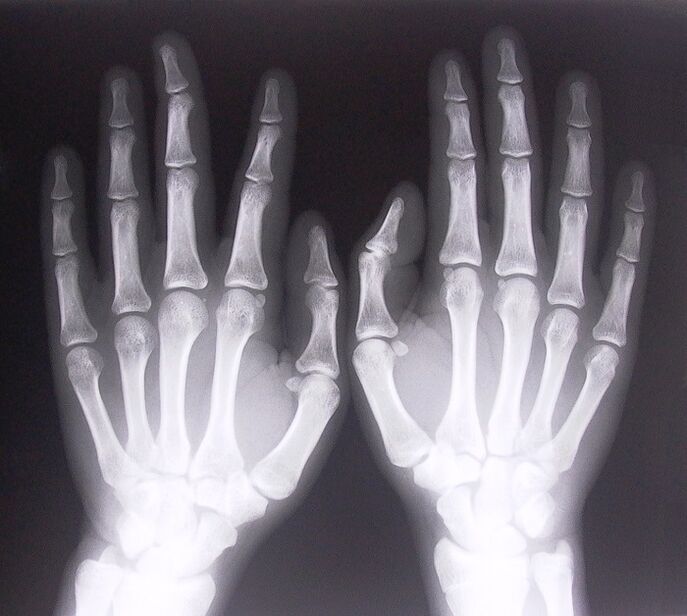

- Stenozuojantis ligamentitas. Norint nustatyti ligos priežastį, būtina atlikti rentgeno tyrimą. Simptomai būdingi: skausmingas rankos judesys, suspausto delno kilpa. Be to, pratęsimo metu dažniausiai girdimi paspaudimai.

- Paimkite rentgeno nuotraukas.